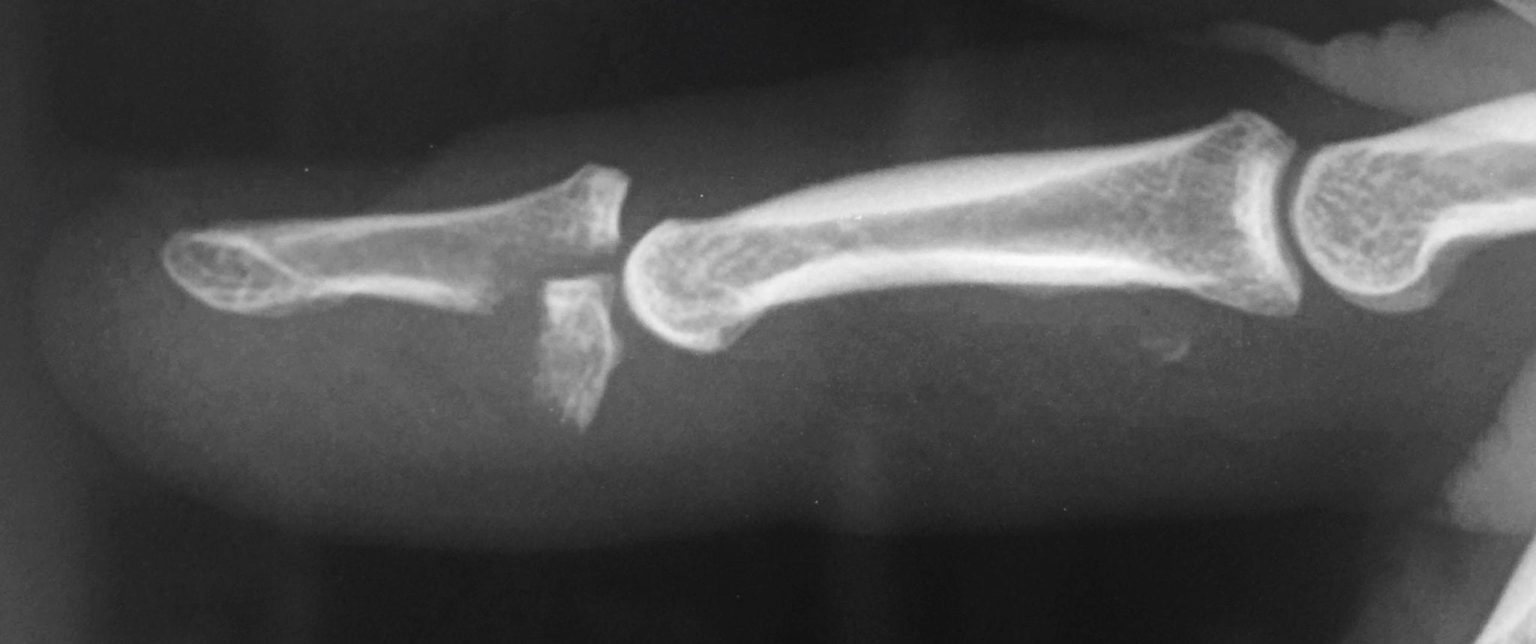

Mallet Finger Xray . The patient with a mallet finger not only has a. Look for evidence of an avulsion fracture on the dorsal aspect of the base of the distal phalanx (=bony mallet). Causes include getting a finger (usually the fourth, or ring, finger) caught in an opponent’s jersey while making a tackle in football or rugby. Mallet finger is a deformity of the finger caused by injury to the extensor tendon or the bone. Refers to damage in the extensor movement of the distal phalanx of the finger, either as a result of injury to the extensor tendon or due. Mallet finger is a finger deformity caused by disruption of the terminal extensor tendon distal to dip joint diagnosis is made clinically when the distal phalanx rests at ~45° of flexion. Posteroanterior (pa) and lateral radiographs centered at the distal interphalangeal (dip) joint of the affected finger.

The patient with a mallet finger not only has a. Mallet finger is a deformity of the finger caused by injury to the extensor tendon or the bone. Refers to damage in the extensor movement of the distal phalanx of the finger, either as a result of injury to the extensor tendon or due. Causes include getting a finger (usually the fourth, or ring, finger) caught in an opponent’s jersey while making a tackle in football or rugby. Posteroanterior (pa) and lateral radiographs centered at the distal interphalangeal (dip) joint of the affected finger. Mallet finger is a finger deformity caused by disruption of the terminal extensor tendon distal to dip joint diagnosis is made clinically when the distal phalanx rests at ~45° of flexion. Look for evidence of an avulsion fracture on the dorsal aspect of the base of the distal phalanx (=bony mallet).

Mallet Finger Xray Look for evidence of an avulsion fracture on the dorsal aspect of the base of the distal phalanx (=bony mallet). Posteroanterior (pa) and lateral radiographs centered at the distal interphalangeal (dip) joint of the affected finger. Causes include getting a finger (usually the fourth, or ring, finger) caught in an opponent’s jersey while making a tackle in football or rugby. Mallet finger is a deformity of the finger caused by injury to the extensor tendon or the bone. Refers to damage in the extensor movement of the distal phalanx of the finger, either as a result of injury to the extensor tendon or due. Mallet finger is a finger deformity caused by disruption of the terminal extensor tendon distal to dip joint diagnosis is made clinically when the distal phalanx rests at ~45° of flexion. The patient with a mallet finger not only has a. Look for evidence of an avulsion fracture on the dorsal aspect of the base of the distal phalanx (=bony mallet).